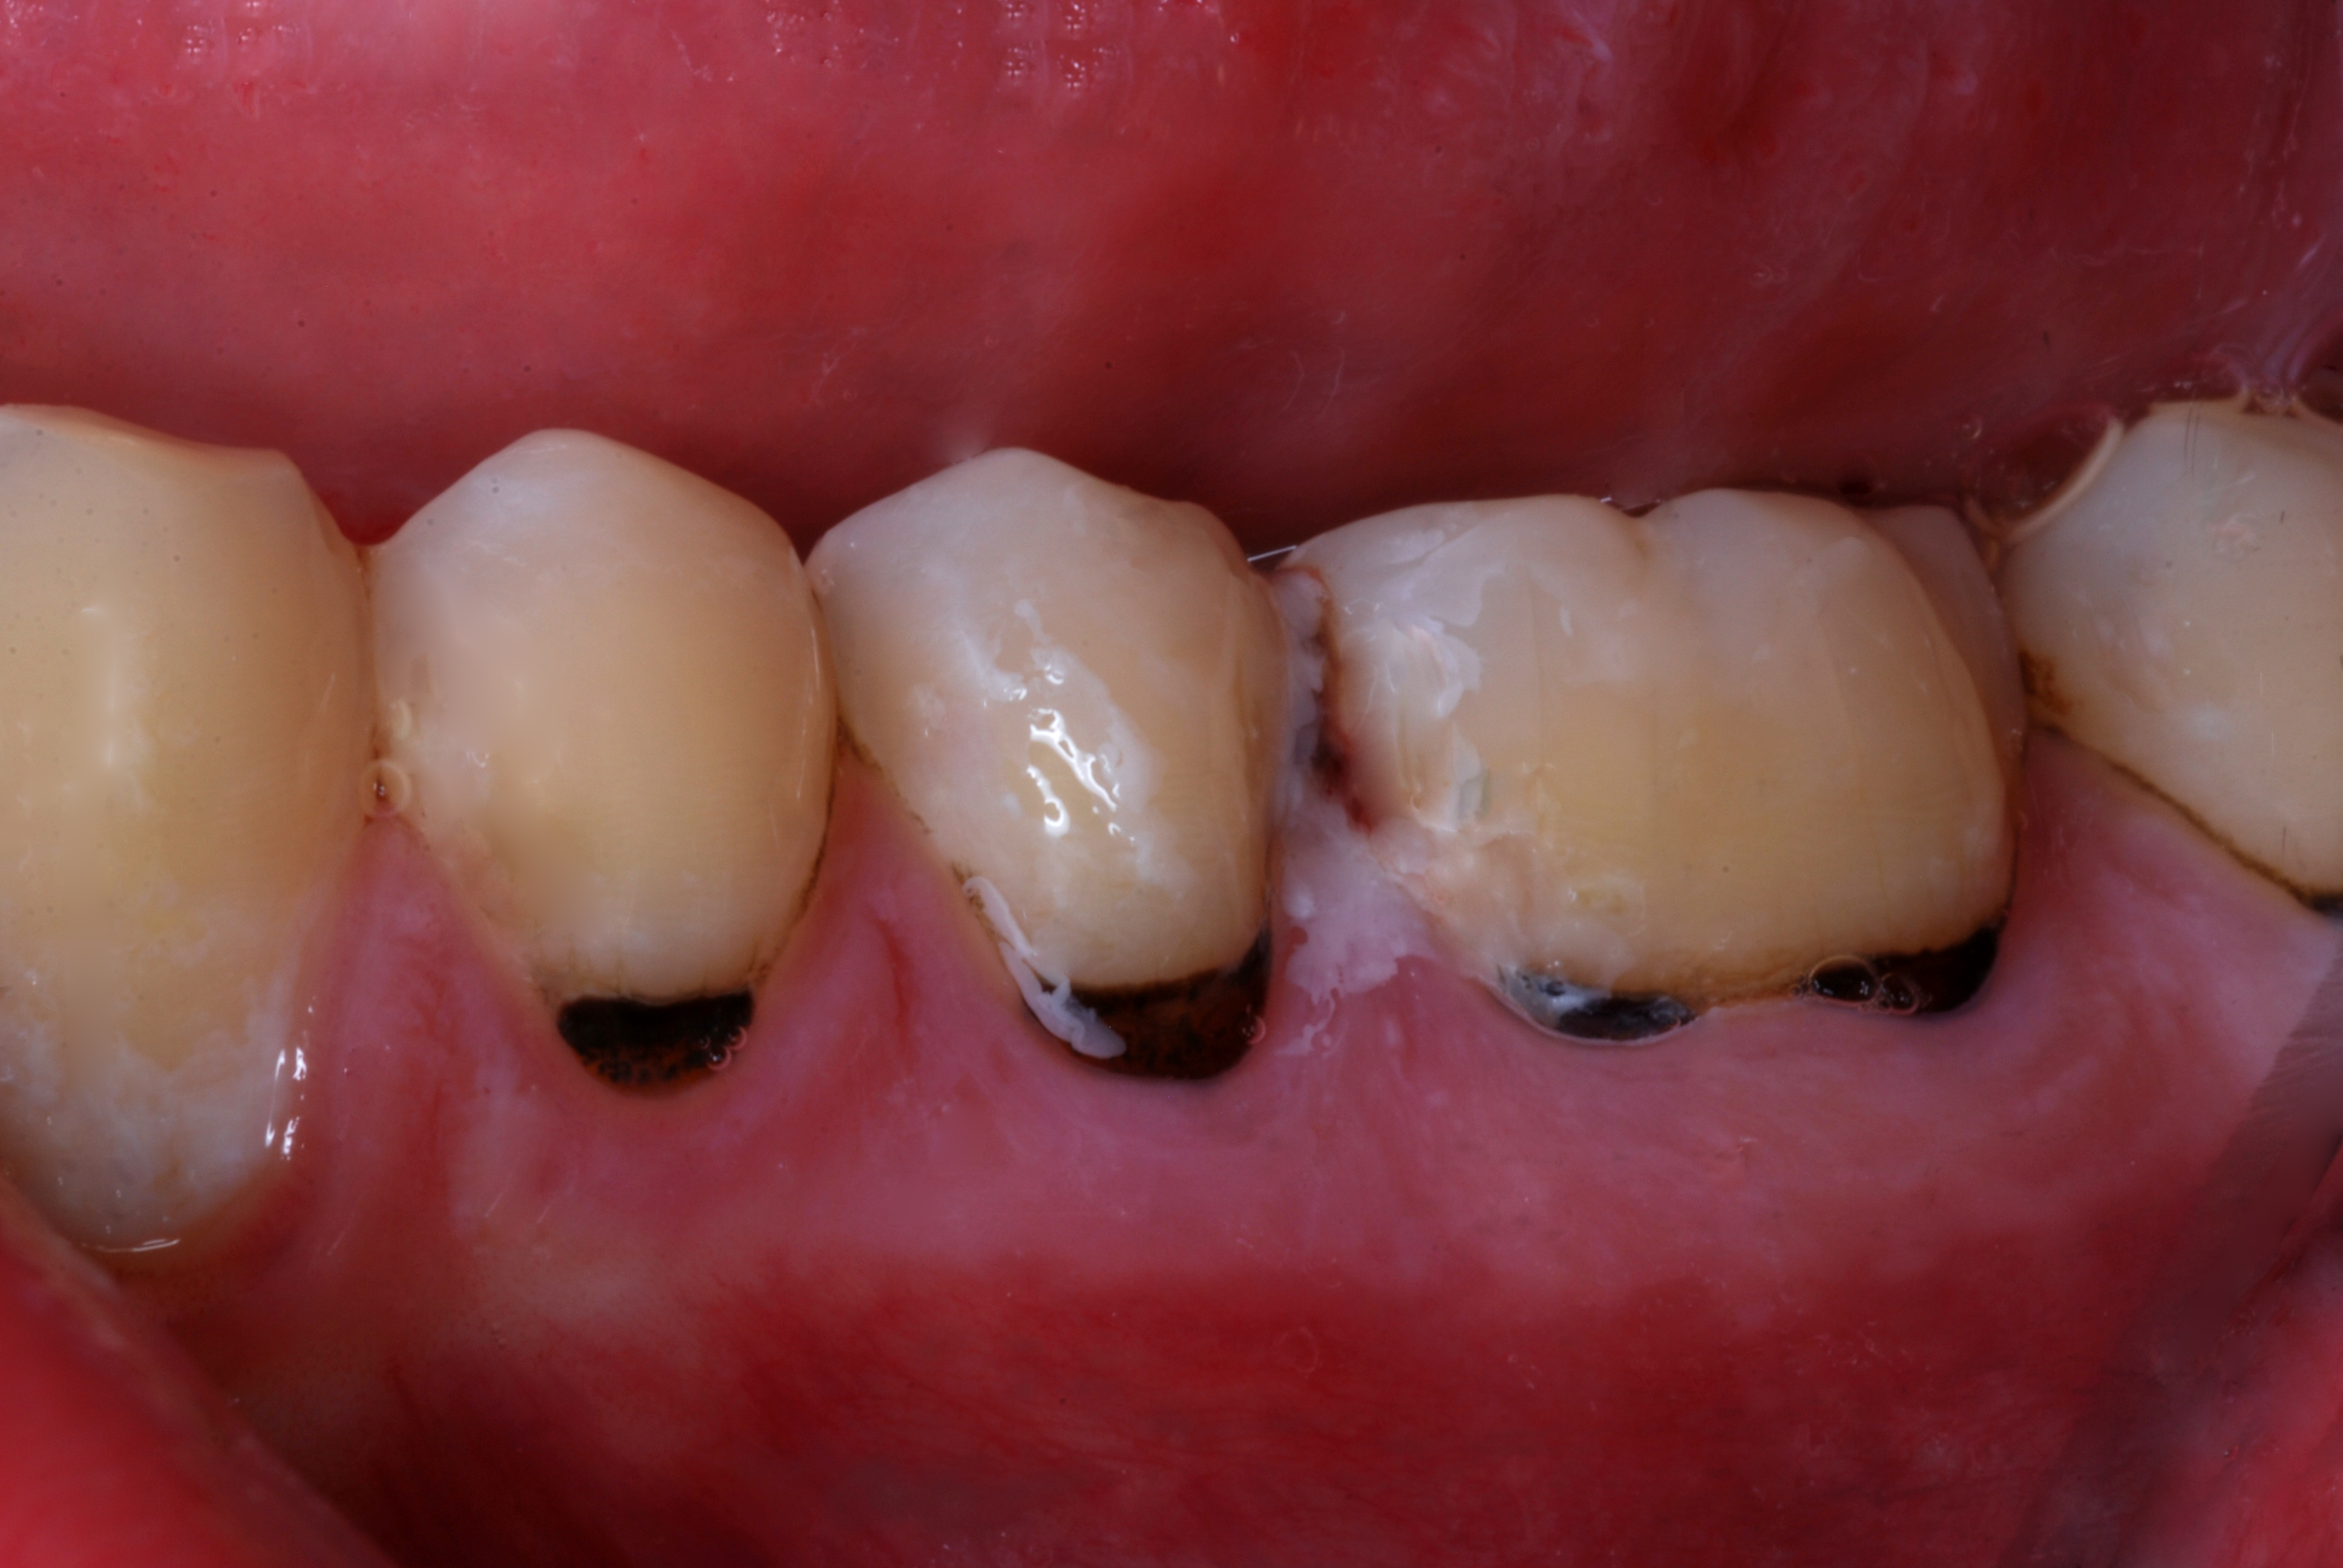

(15.) A 21-year-old patient returned for a second SDF/fluoride varnish treatment for cervical caries, 3 months after initial SDF application. The patient needed to delay restorative care for “personal reasons.”

Figure 15

(16.) A 21-year-old patient returned for a second SDF/fluoride varnish treatment for cervical caries, 3 months after initial SDF application. The patient needed to delay restorative care for “personal reasons.”

Figure 16